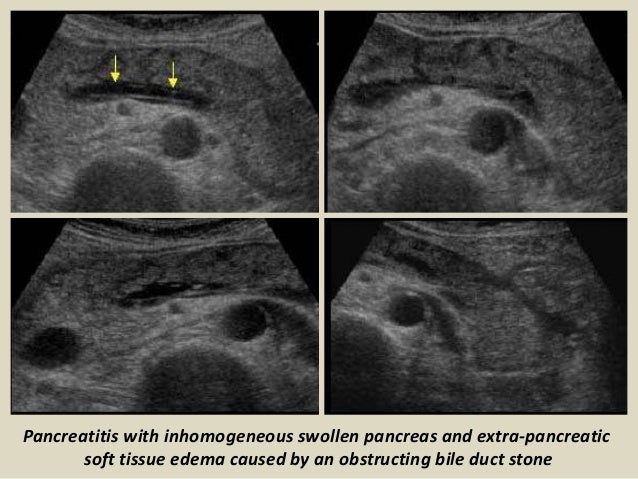

- Pancreatitis, or inflammation of the pancreas: This happens when digestive enzymes start digesting the pancreas itself

Diagnosis of pancreatic diseases is based on increasing or decreasing echocardiography of the organ. If the organ is healthy, then normal echogenicity is observed. With increased parenchyma density or replacement of normal tissues with fat or connective, echogenicity increases. If echolineses of MI indicate a decrease in parenchyma, then this indicates inflammatory processes in the pancreas, acute or chronic pancreatitis. Depending on the severity and nature of diffusion, it is possible to diagnose not only pancreatitis, then diabetes mellitus, tumors, fibrosis and abscesses.

Why is the pancreas denser?